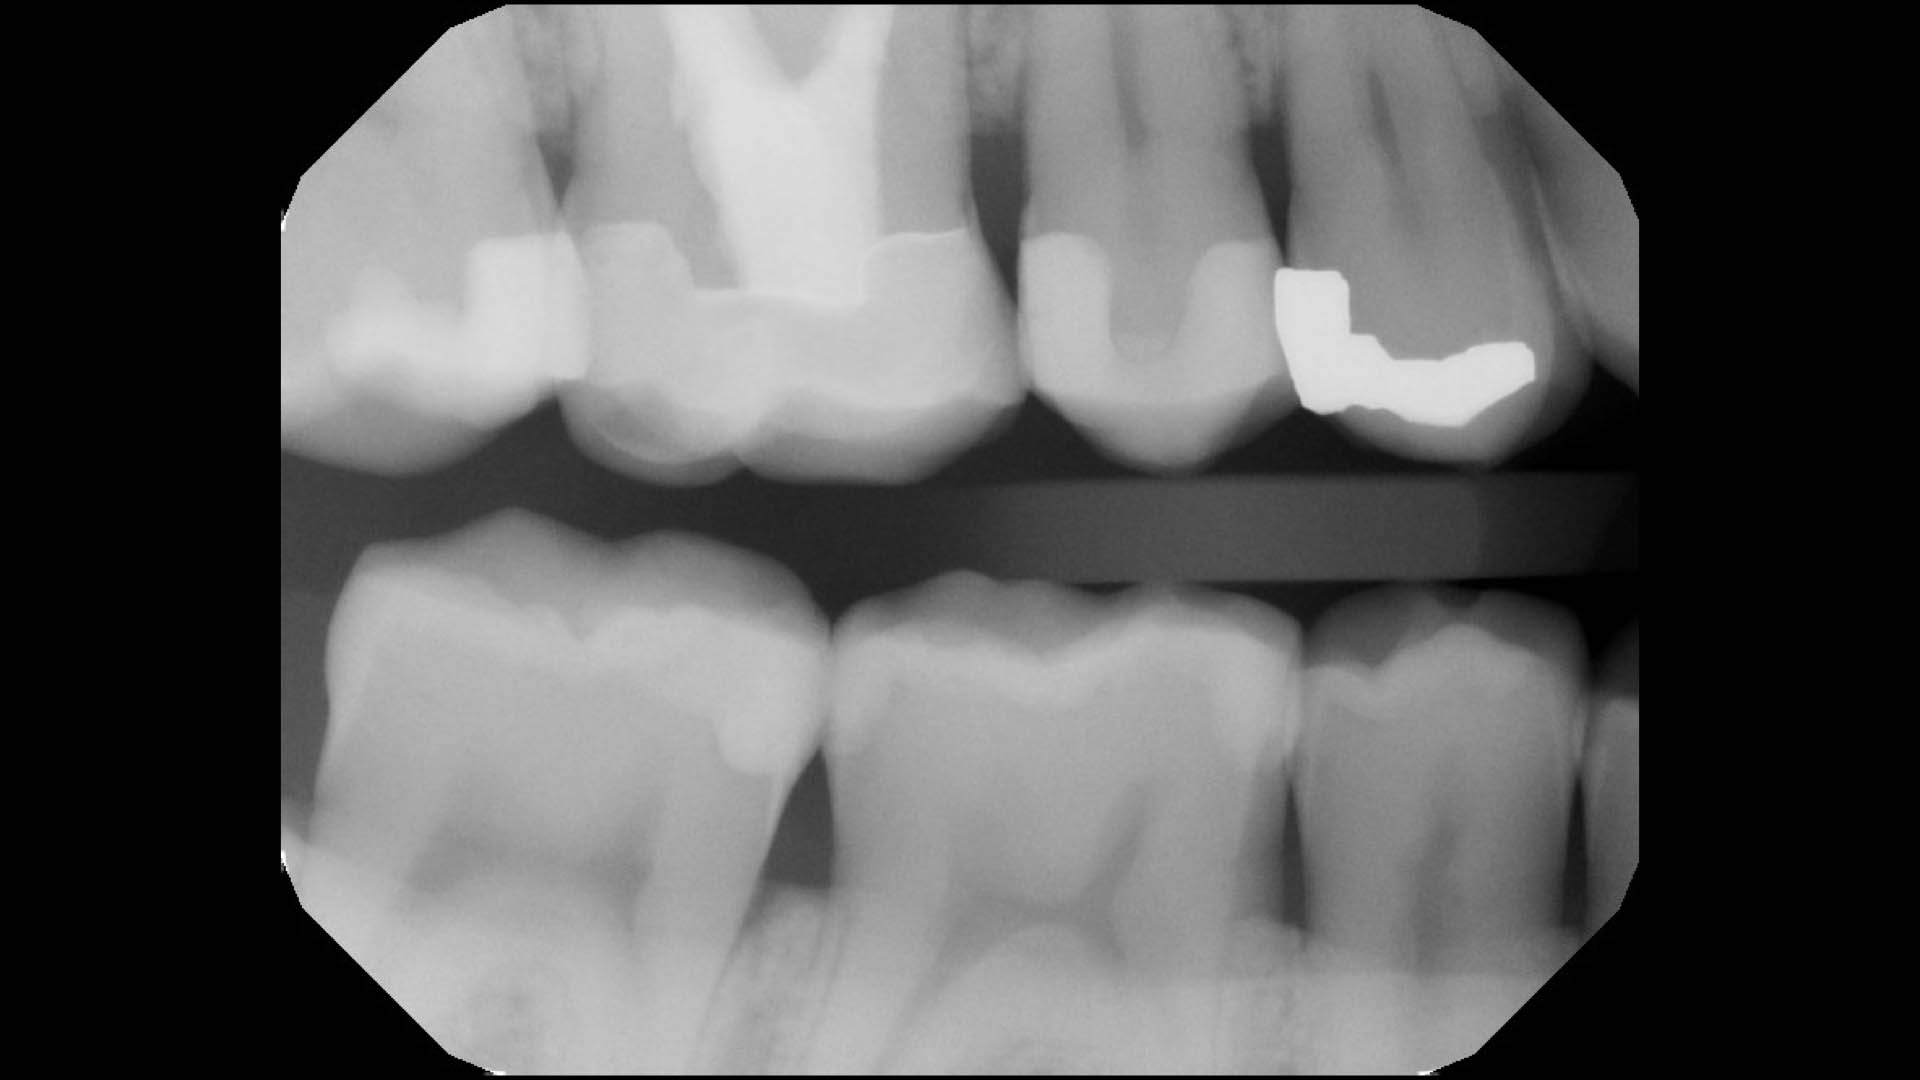

Take a glimpse into the magic of Coral Gables Dentistry through our before and after pictures. See firsthand the incredible smile makeover transformations that have brought confidence and joy to our patients.